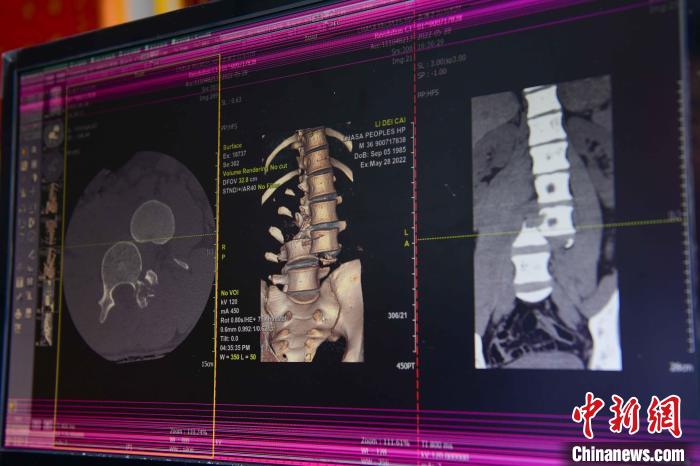

圖為患者術(shù)前,腰3/4脊柱骨折伴脫位?!≡髑?攝

通道開通后,拉薩市人民醫(yī)院完成了兩例脊柱創(chuàng)傷截癱患者的救治。一例23歲的病患為胸12椎體爆裂骨折伴截癱,另一例36歲的病患腰椎體骨折脫位伴雙下肢癱。按照脊髓損傷救治綠色通道流程,術(shù)前充分快速完善相關(guān)檢查,充分術(shù)前評估,向患者詳細交代手術(shù)風險,入院當天急診行手術(shù)治療。